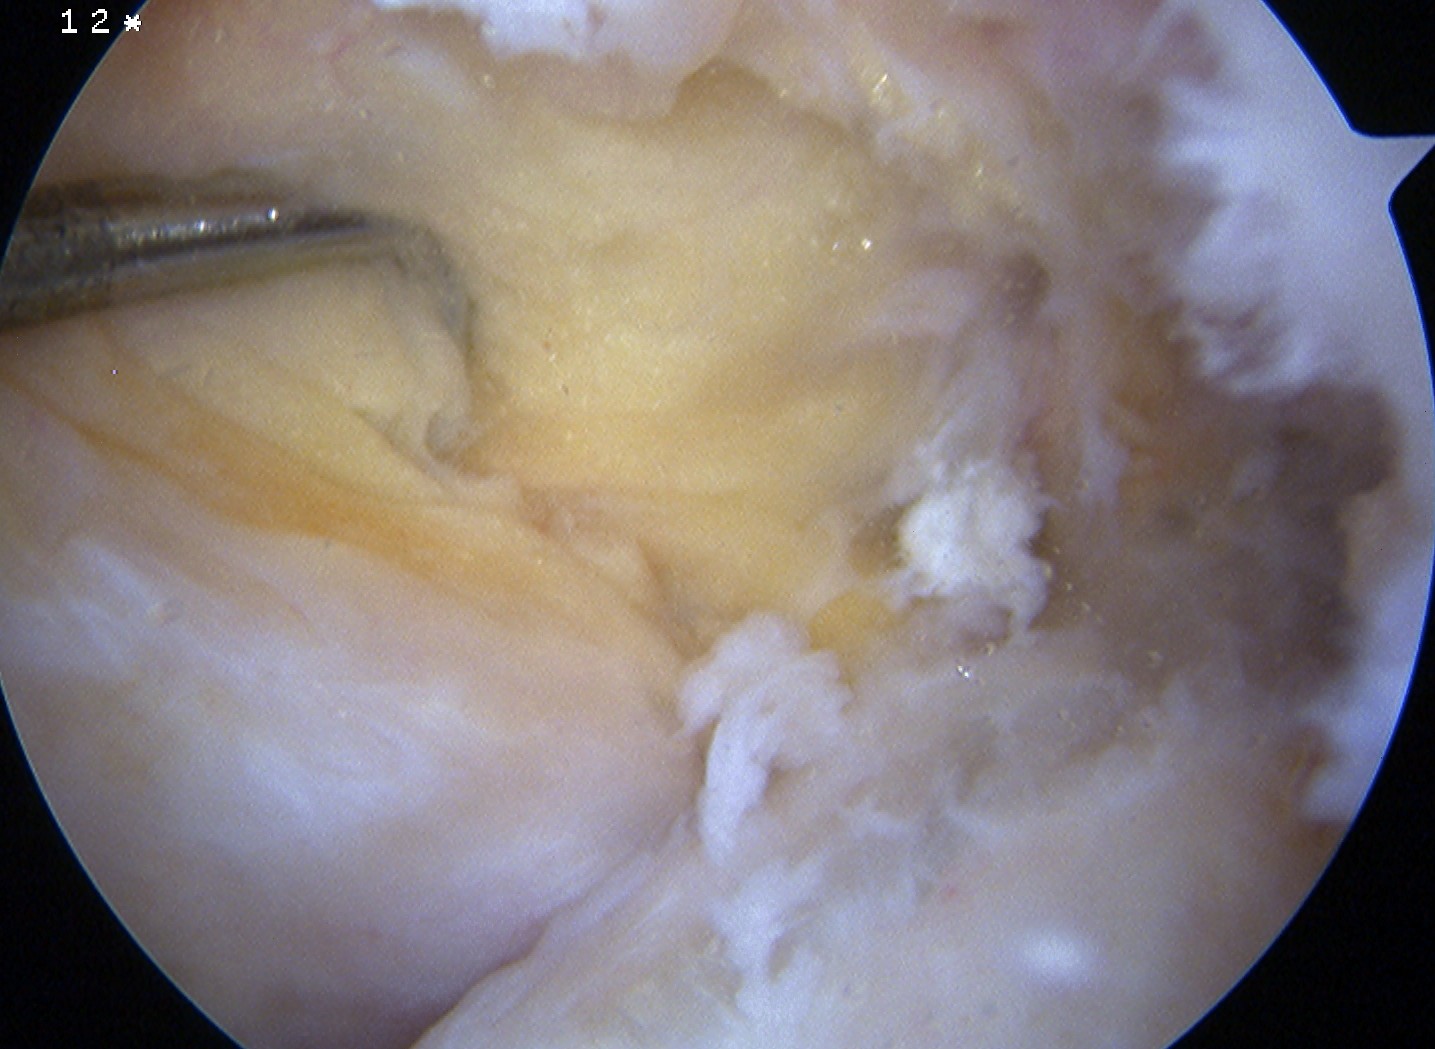

Arthroscopy

May miss tear as is extra-synovial

Chronic PCL tear from femur

Acute PCL femoral avulsion

Apparent ACL laxity due to PCL tear and posterior tibial sag; ACL tension restored with anterior drawer